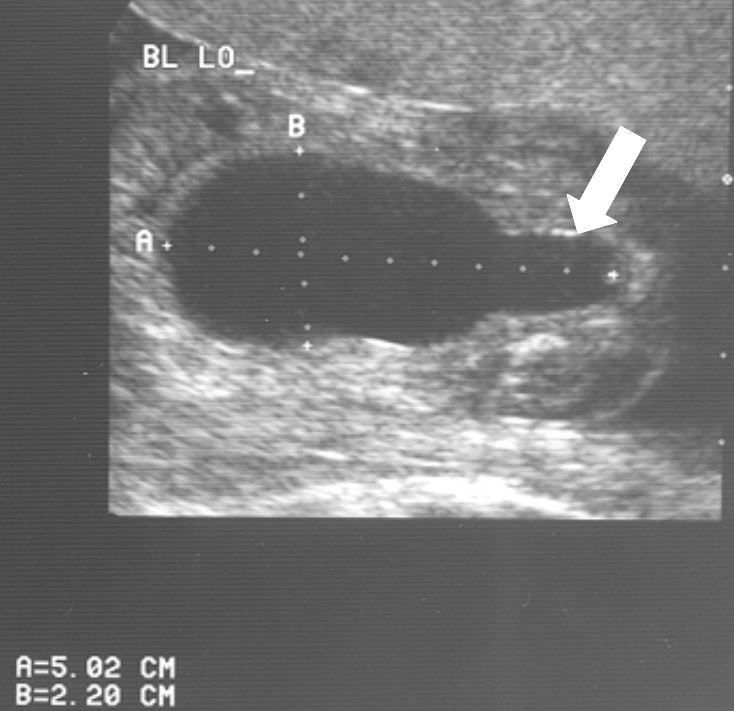

Veel ernstige vormen van urethrakleppen worden al gezien bij echografisch onderzoek vóór de geboorte. Bij de 20 weken echo (of misschien in de toekomst bij een 13 weken echo) worden verwijde nierbekkens en urineleiders gezien. De blaas kan dikwandig zijn, maar ook zeer groot en uitgerekt. Vaak kan het verwijde deel van de plasbuis ónder de blaas worden gezien. Dat noemen we het “sleutelgat teken” omdat de blaas in lengtedoorsnede op de echo er dan uitziet als een sleutelgat. De hoeveelheid vruchtwater kan normaal of verminderd zijn. Als er een verdenking is op urethrakleppen wordt de bevalling gedaan in een centrum waar direct optimale zorg kan worden geleverd aan de pasgeborene.

20 weken echografie: links: dikwandige blaas met verwijding van de plasbuis tot aan de kleppen (pijl): het “sleutelgat teken”. Onder: verwijde urineleiders. Bij kinderen gaan de urineleiders bij verwijding ook erg gekronkeld verlopen.

Verwijde nierbekkens (lange pijl) en nierkelkjes (korte pijl). Smalle nierschors.